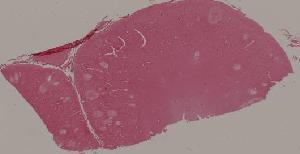

72.狼疮性肾炎